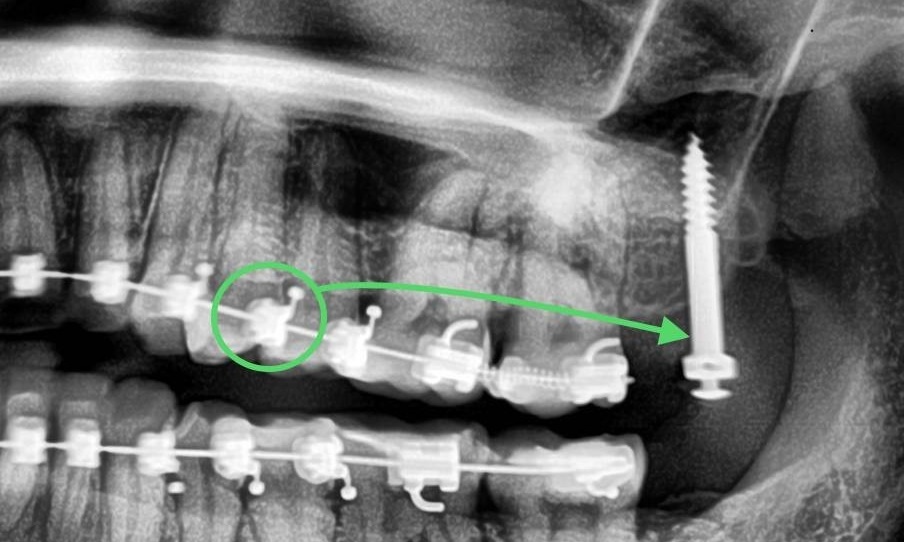

Схематичное изображение на рентгенограмме тяги от верхнего первого премоляра к минивинту.

Рентгенограмма сделана сразу после установки 2 минивинтов в области зуба 1.7 (вестибулярно и нёбно). Такое расположение даёт нам возможность равномерно внедрить экструзированный зуб.